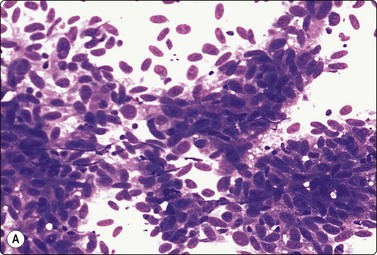

image image

Fig. 6.18 Follicular neoplasm

Cellular smears of single cells, microfollicles or rosettes in a repetitive manner; benign adenoma by histology (A, MGG, HP; B, Pap, HP).

Fig. 6.19 Follicular neoplasm

Smears very similar to Figure 6.18; follicular carcinoma with vascular invasion by histology (A, MGG, HP; B, Pap, HP).

FNs are classified as benign (FA) and malignant (FC). FAs and most FCs are encapsulated tumors, occurring in one of the lobes. Histological diagnosis of a well-differentiated FC requires demonstration of capsular and/or vascular permeation. Most FNs, especially adenomas, have a uniform internal structure that is reflected in the cytological smears. FAs are more common in women and microscopically show a variety of histological patterns such as microfollicular (fetal), normofollicular, macrofollicular, trabecular, solid (embryonal), Hurthle cell and atypical adenomas.42 Cytologically, follicular lesions include FA, FC, cellular NG and FV-PC.121

Smears in FN are cellular in a bloody background that is usually devoid of colloid. Many uniform-sized follicular cell clusters, microfollicles and rosette formations are present. Syncytial aggregates, nuclear crowding and overlapping are also often seen.

The repetitive smear pattern with uniform cell population is in contrast to the variable pattern of different cell types seen in colloid and hyperplastic nodules. Microacinar clusters with a central lumen (that may contain a drop of colloid) represent microfollicles (Figs 6.18, 6.19 and 6.21B). These are characteristic of FN but may be found focally in NG. Rosette-like groupings without a lumen (Fig. 6.20) suggest a more solid growth pattern. A trabecular pattern is represented by rows and elongated aggregates of epithelial cells that resemble papillary structures when they adhere to strands of vascular stroma (see Fig. 6.33B,C). Small blood vessels with adherent epithelial cells can be found in any type of follicular neoplasm (see Fig. 6.25A).